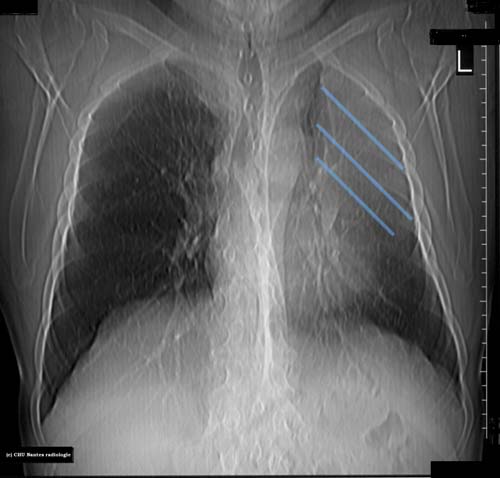

Atélectasie

Opacité triangulaire à sommet hilaire et à base pariétale à limite nette avec rétraction pulmonaire sans bronchogramme aérien : atélactasie compléte lobaire supérieure gauche